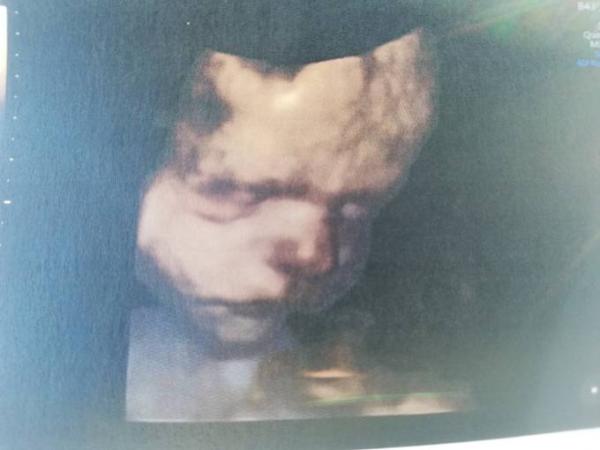

Hallo Zusammen, Ich war heute mal wieder zur Vorsorge und wie liegt der kleine Mann? Ich bin in der 31Ssw und der denkt sich Querlage ist doch schön Außerdem ist er ca. 1700gramm schwer und misst 38cm. Mögt ihr mir eure Maße und Lagen verraten wenn ihr sie wisst? Ganz liebe Grüße von mir und dem kleinen Grummler

Bild zu Kindslage - Forum für April - Mamis

Das sind doch optimale Maße Und ein sehr süßes Bild von ihm! Bei mir lag er auch immer in querlage, heute war das erste mal das er mit dem Kopf nach unten lag. Dein Spatz dreht sich bestimmt noch Meine Werte sind heute bei 31+2: 42 cm und 2,1kg

Sehr süßes Bild Bei 32+2 hatte meine Kleine um die 2400g und 45 cm! Seither war ich nicht mehr beim Arzt! Sie liegt jetzt seit der 30 Woche in Schädellage!